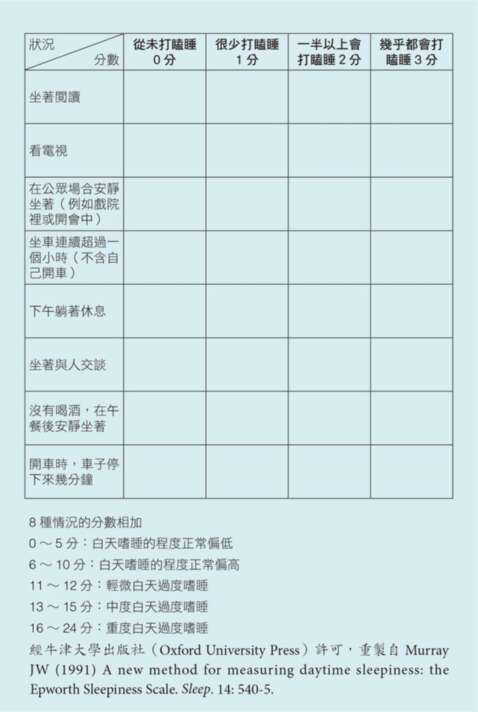

我們也可以觀察自己的行為模式,有些徵兆,確實是身體在告訴我們——該睡了。我們可以一起來做這個「有多想睡」的問卷。

艾普沃斯嗜睡量

依照下列8種狀況,我們試著描述自己可能會打瞌睡的程度(不只是疲累,而是真的會打瞌睡)。每種狀況,依照自己最近這幾個月的反應,選擇一個最貼近的答案。如果有些狀況不會發生在你的生活,也試著揣摩看看,當自己在這種狀況時,會是怎樣的反應。

填完這個量表,相信你可以體會到,如果在各種情況下都會打瞌睡,那麼已經是相當疲倦而想睡,甚至可能是生理調控出了狀況而導致的嗜睡。我在這裡還是要提醒:現代的社會步調相當快,對任何事都過度追求一個快速的解答。疲勞,也是一樣。我們等不及放鬆,等不及睡眠,各種提神飲料、咖啡、抽菸,成為一般人最快的選擇。然而,有時候,我們需要的其實只是小睡片刻。